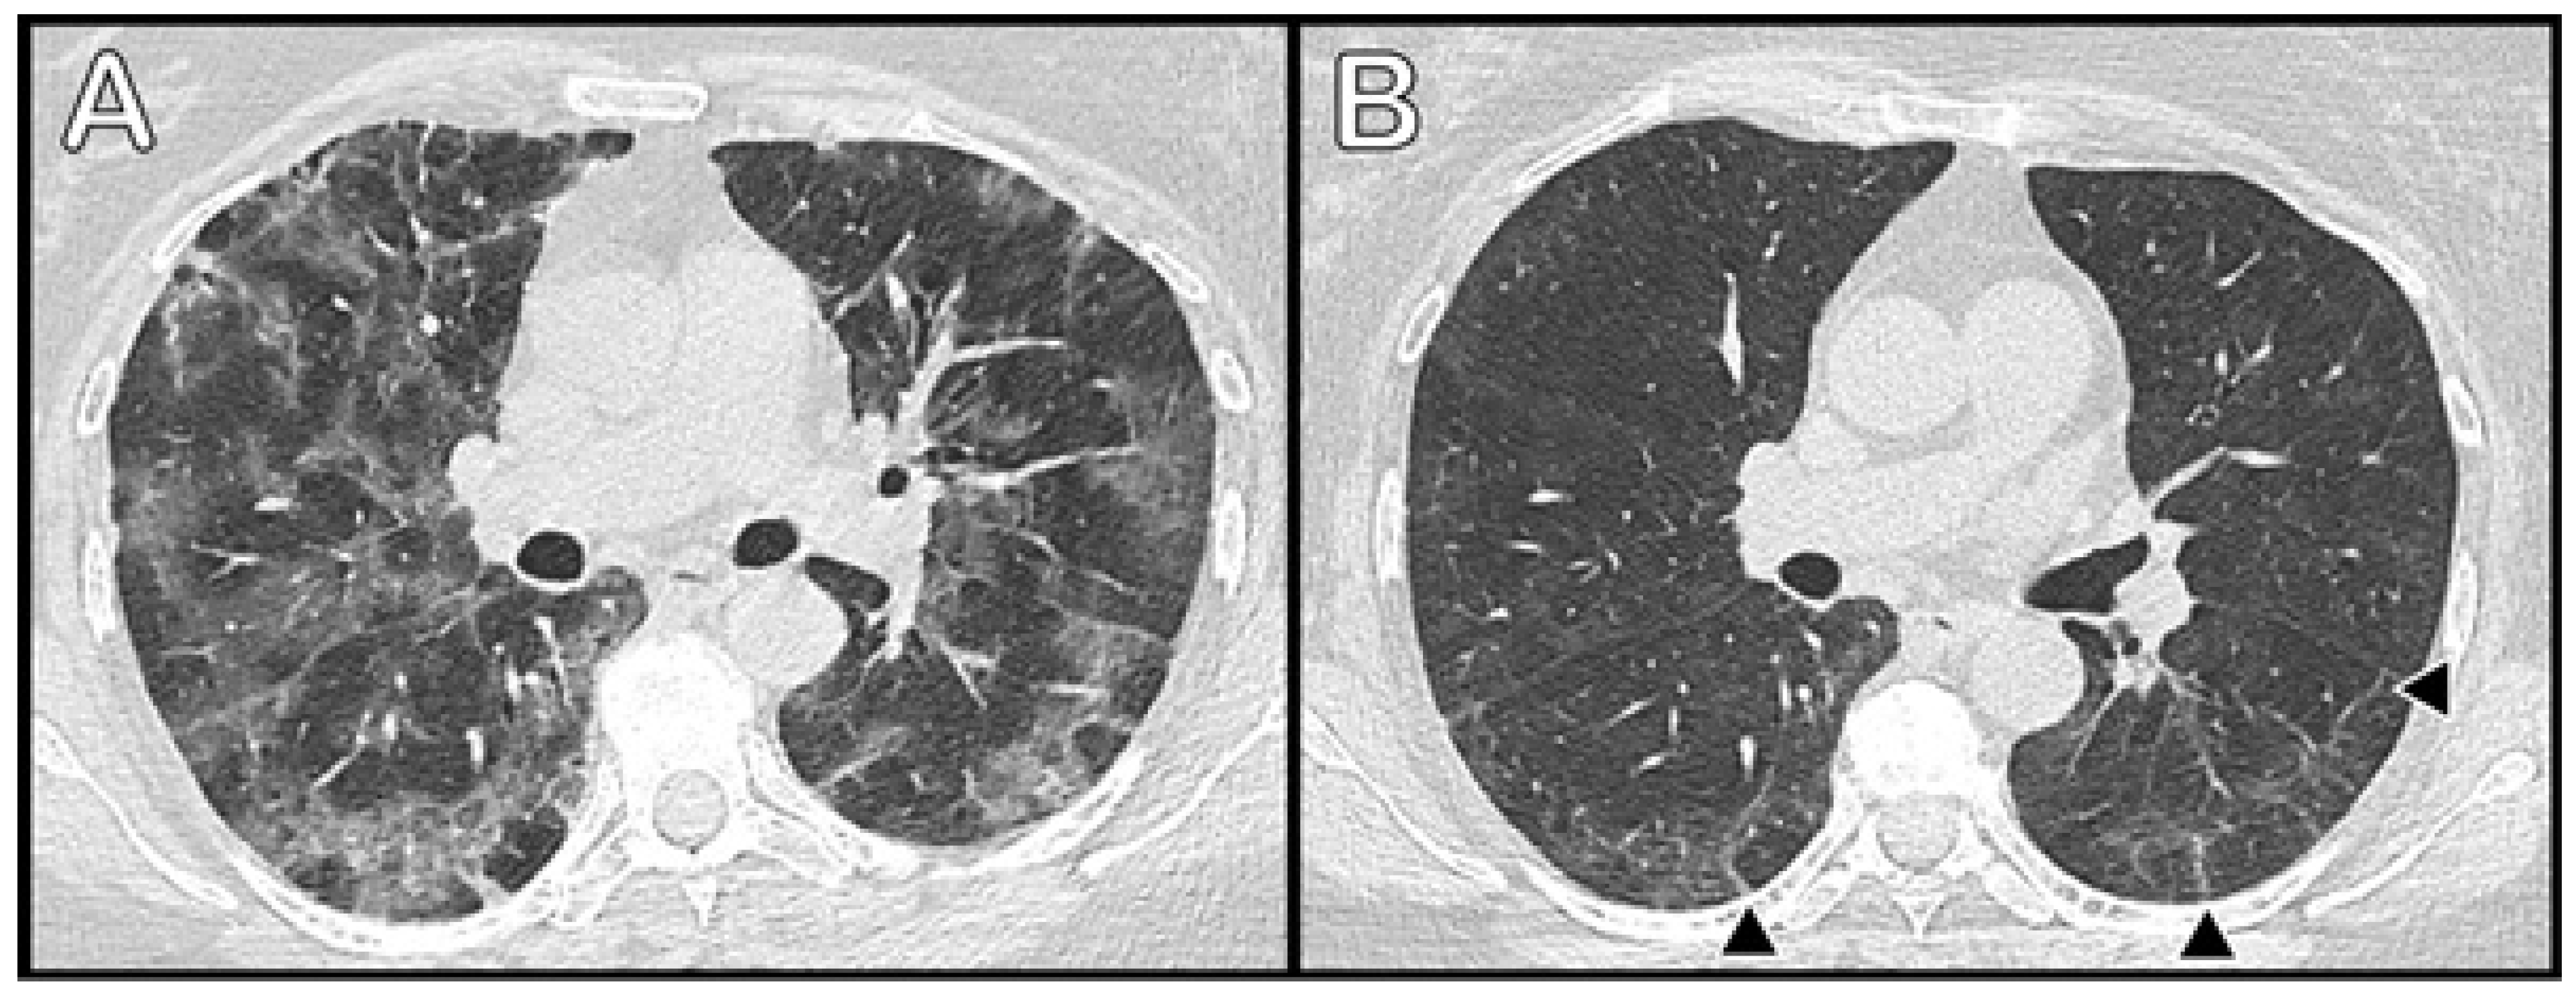

3.3. Radiological Data

3.4. Health-Related Quality of Life